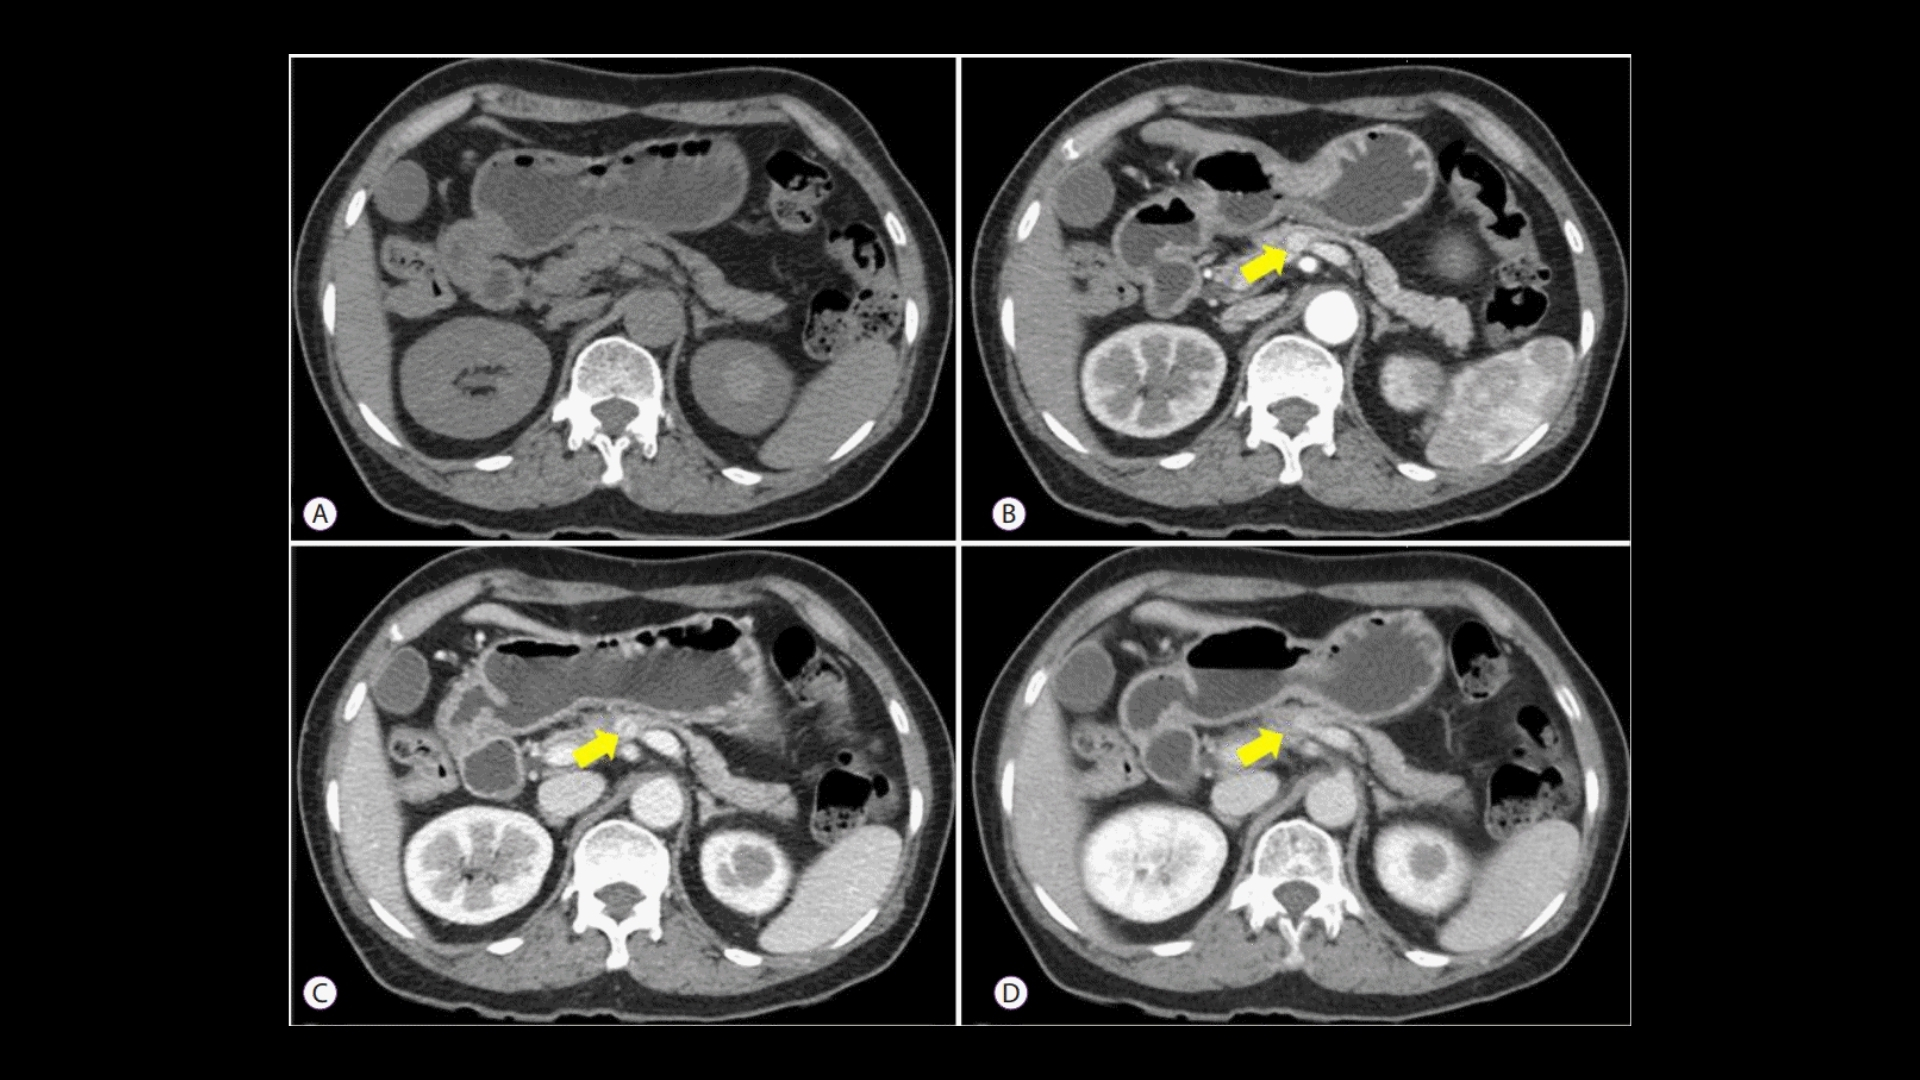

• 進階診斷:最先進的影像(例如 PET-CT、Siemens MRI)和分子剖析,以找出腫瘤的代謝漏洞。